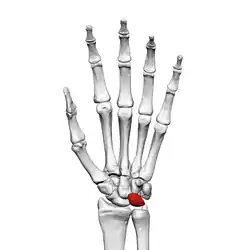

![]() The left lunate bone | |

Bone

The proximal surface of the lunate bone is smooth and convex, articulating with the radius. The lateral surface is flat and narrow, with a crescentic facet for articulation with the scaphoid bone. The medial surface possesses a smooth and quadrilateral facet for articulation with the triquetral bone. The palmar surface is rough, as is the dorsal surface. The dorsal surface is broad and rounded. The distal surface of the bone is deep and concave.[4]